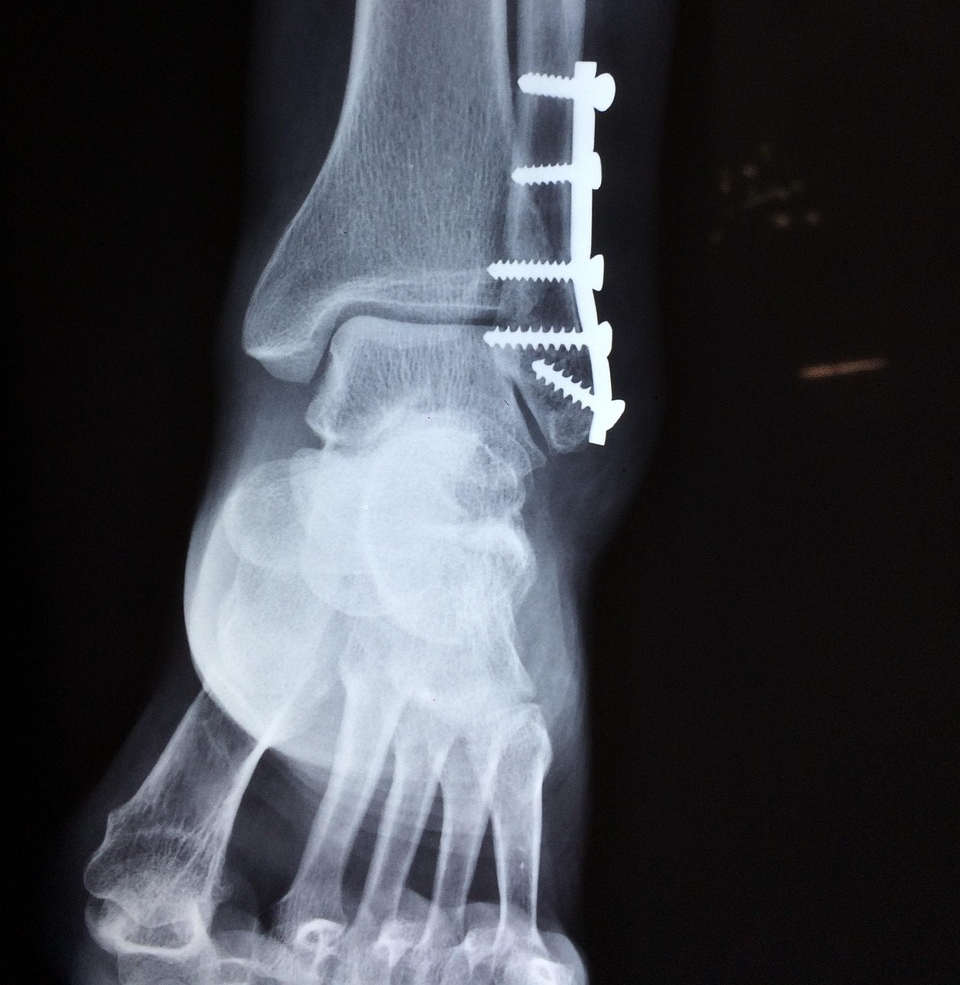

- X-ray(엑스레이): 뼈 골절 여부 확인.

- 수술: 인대 완전파열, 반복 염좌, 관절 불안정증이 있을 때 고려.